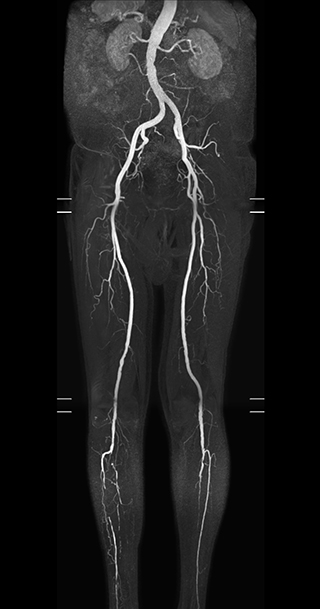

MRA of foot with 4D-TRAK XD

The images obtained with Ingenia Ambition show large coverage and high uniform signal. More vessels are visible than in a previous exam of the same patient on Achieva. The movies show a higher temporal resolution in the Ambition acquisition than in a previous Achieva 1.5T exam. Both exams use a FOV of 300 mm and voxel height and width of 0.78 mm.

Achieva 1.5T

2:30 min. TE 1 ms, TR 4 ms

Ingenia Ambition

4D Trak XD 1:54 min. TE 1ms, TR 3ms

Another example is the foot examination for diabetic patients, which has improved dramatically. “The forefoot is generally difficult to image with MRI because of the inhomogeneities that the toes create – it’s hard to obtain good fat saturation in that area. Here, mDIXON made a huge difference right away, we obtain much better image quality,” Dr. Peña says. “Using mDIXON, Compressed SENSE and the dS FootAnkle coil, we have been able to reduce the scan time, so that we can now also include an additional 3D STIR sequence to visualize both arteries and veins in the foot.”

Avila adds: “In addition, since most of these patients are in a significant amount of pain, it’s important to perform the examination as quickly as possible. With Compressed SENSE and mDIXON we have been able to reduce the scan time from about 45 minutes to just 15 minutes. Not only does this improve patient comfort, we see that it also helps us acquire images without motion artifacts, which is critical to making a confident diagnosis.”